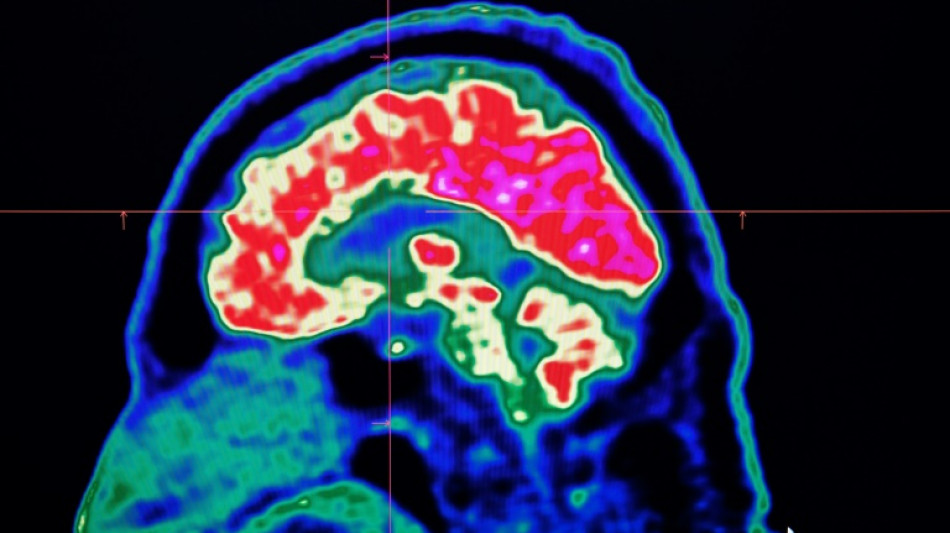

Surging nervous system disorders now top cause of illness: study / Photo: Fred TANNEAU - AFP/File

Conditions affecting the nervous system -- such as strokes, migraines and dementia -- have surged past heart disease to become the leading cause of ill health worldwide, a major new analysis said on Friday.

More than 3.4 billion people -- 43 percent of the global population -- experienced a neurological condition in 2021, far more than had previously been thought, the analysis found.

Lead study author Jaimie Steinmetz of the IHME said the results showed that nervous system conditions are now "the world's leading cause of overall disease burden".

Cases of these conditions have soared by 59 percent in the last three decades, she said, with the increase mainly driven by the fact that the world's population was ageing and growing fast.

The researchers looked at how 37 different neurological conditions affected ill health, disability and premature death across 204 countries and territories from 1990 to 2021.

This data was used to estimate how many years of healthy life were lost to each condition, called disability-adjusted life years (DALYs).

More than 443 million years of healthy life were lost to nervous system disorders globally in 2021, an 18-percent increase from 1990, the study found.